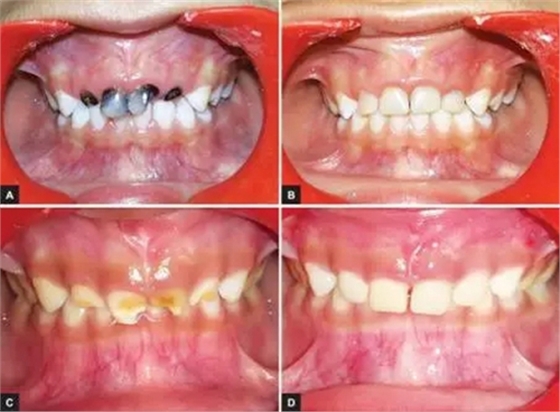

本研究中,其他患齲齒或牙外傷的患兒均采用此方法使用臨時冠材料進行美學修復,下圖分別為兩例乳前牙齲齒(圖2)和兩例牙外傷(圖3)的病例。

圖2.(2-A,2-B為乳前牙齲齒病例1 2-C,2-D為乳前牙齲齒病例2)